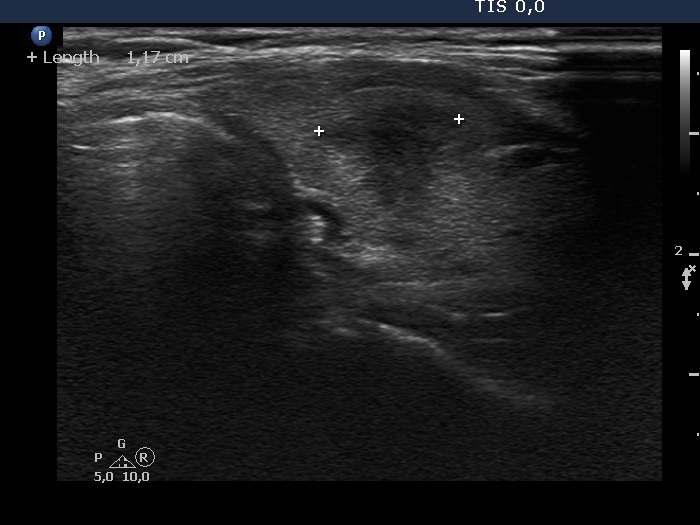

The borders of the nodule - case 2022 (ultrasonographic picture 5)

Right lobe, oblique view.